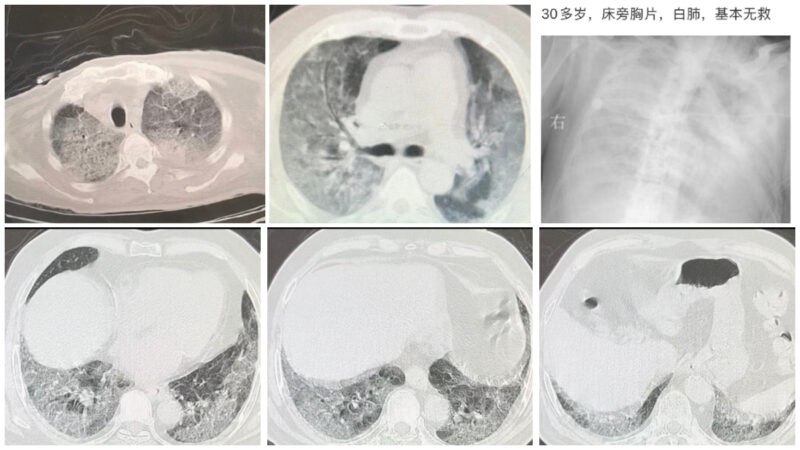

【新唐人北京时间2022年12月24日讯】中国最新一轮疫情大爆发,许多感染者被诊断为严重肺炎,三年前武汉疫情爆发时的典型症状“白肺”再度大量涌现。不少医护人员纷纷贴出医院拍下的照片,显示有患者肺部已彻底纤维化,相当恐怖。

所谓“白肺”,是指重症肺炎患者进行X光检查时,肺部显影呈现一大片白色。这意味着肺部已被炎症严重侵蚀,性命堪忧。

来自四川的神经外科医师“不神经的神经科医生”23日连续在微博发布两张“白肺”照片,其中一张显示肺部完全变白,但患者只有30多岁。帖文称:“30多岁,床旁胸片,白肺,基本无救 。”

另一张照片也显示肺部开始白化。帖文指:“刚刚急诊科收进来的一个重症肺炎,没有核酸,当然不能诊断新冠,只能叫重症肺炎,很遗憾,这个病人氧饱和度只有78%(注:正常是99%)。”